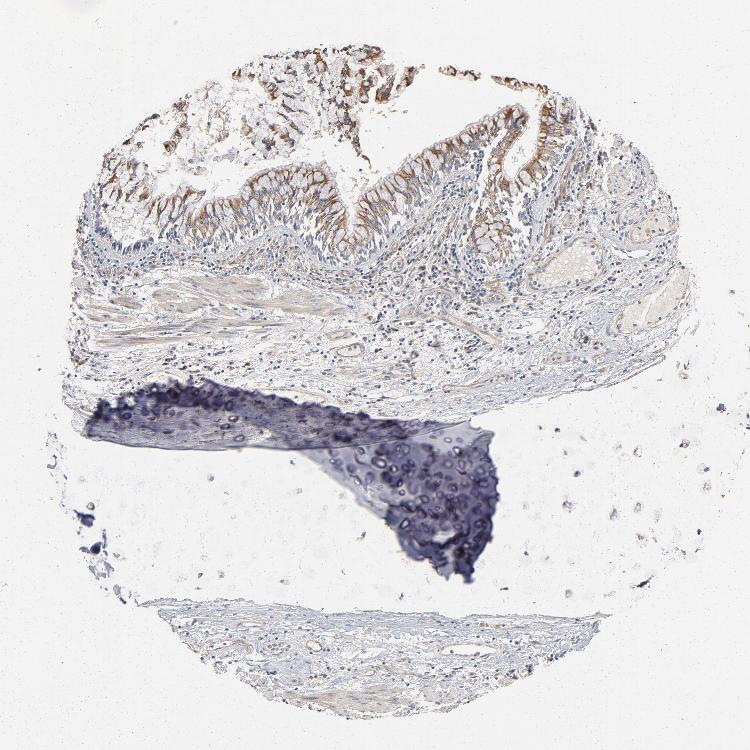

ADIPOSE TISSUE - Antibody stainingi

Antibody staining in the annotated cell types in the current human tissue is reported as not detected, low, medium, or high, based on conventional immunohistochemistry profiling in selected tissues. This score is based on the combination of the staining intensity and fraction of stained cells.

Each image is clickable and will lead to virtual microscopy that enables deeper exploration of all samples and also displays staining intensity scores, fraction scores and subcellular localization as well as patient and tissue information for each sample.

Antibody HPA003936

Adipocytes Medium